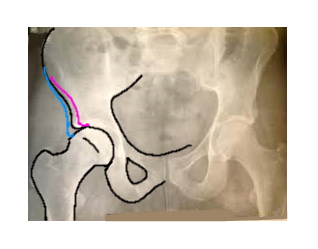

Moins la hanche enveloppe la tête du femur,

plus les pressions sont concentrées sur une partie du cartilage

et plus le risque d'usure et de destruction est grand. ©Laurence Grard Guenard